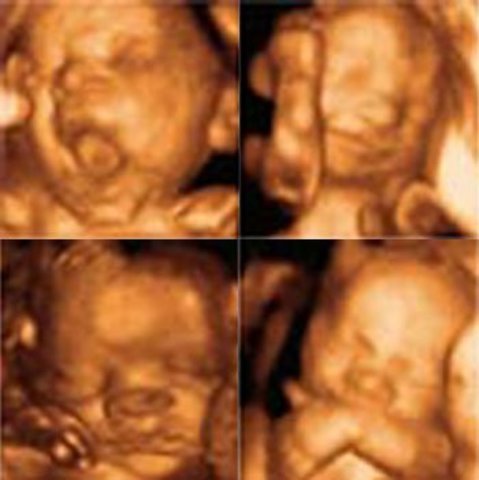

El feto mide casi 11 cm y pesa un poco más de 50 g. Su cabeza mide 3,5 cm de diámetro, ya puede moverla, lo mismo ocurre con sus brazos, manos y piernas. También es capaz de mover los dedos, que ahora sí están ya completamente separados.

Su boca se cierra y se abre y se empiezan a elaborar los pigmentos de la piel.